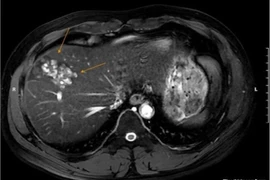

Nam bệnh nhân 41 tuổi ở Hà Nội mới đây được phát hiện tổn thương gan nghiêm trọng do nhiễm sán lá gan lớn vì thói quen ăn đồ sống thường xuyên.